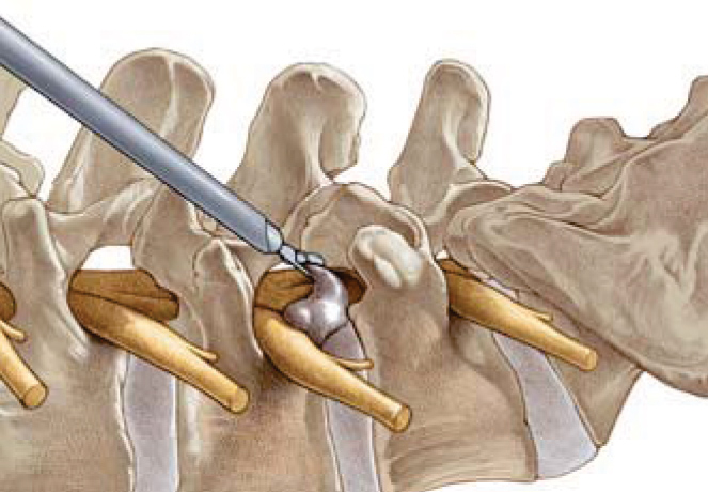

安全三角安全三角工作区的界限:前界为出口神经根;下界为下椎体的上终板;内界延伸为行走神经根与硬膜囊。

总述椎间孔镜技术是将一个配备有灯光、成像及工作通道的孔镜系统经病人身体侧方或者侧后经椎间孔放置于突出的椎间盘部位,在内窥镜直视下,可以清楚地看到突出的髓核、受压的神经根、硬膜囊和增生的骨组织,然后使用各类抓钳经孔径的工作通道摘除突出髓核组织、绞除部分增生的上关节突骨质、切除部分增厚的黄韧带,扩大狭窄的神经根管,从而直接解除神经根的压迫,同时可对病变部位进行持续灌洗消炎,运用射频电极修补纤维环,消融神经致敏组织,阻断环状(窦椎)神经分支,解除患者软组织的疼痛。